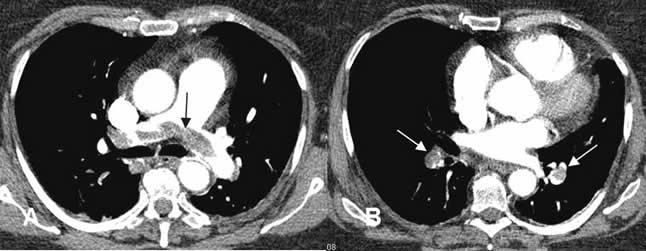

Fig 141. Tromboembolismo pulmonar.

A y B: TAC axial. Defectos de repleción en la arteria pulmonar y sus ramas principales, por TEP masivo.